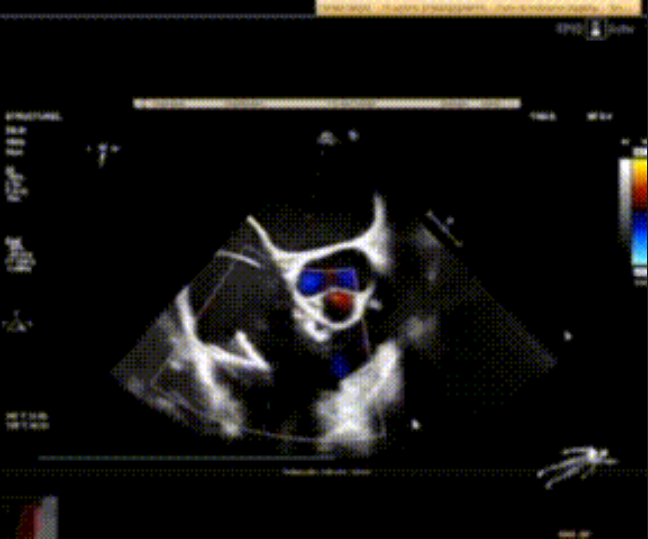

術(shù)前心臟超聲提示:極重度三尖瓣返流,右房容積明顯增大,三尖瓣瓣環(huán)顯著擴(kuò)張。

術(shù)后心臟超聲提示:LuX-Valve Plus植入后,三尖瓣瓣環(huán)處可見人工瓣膜回聲,未見返流,人工瓣膜穩(wěn)定,瓣葉開閉良好,連續(xù)多普勒估測三尖瓣平均跨瓣壓差僅為1mmHg。